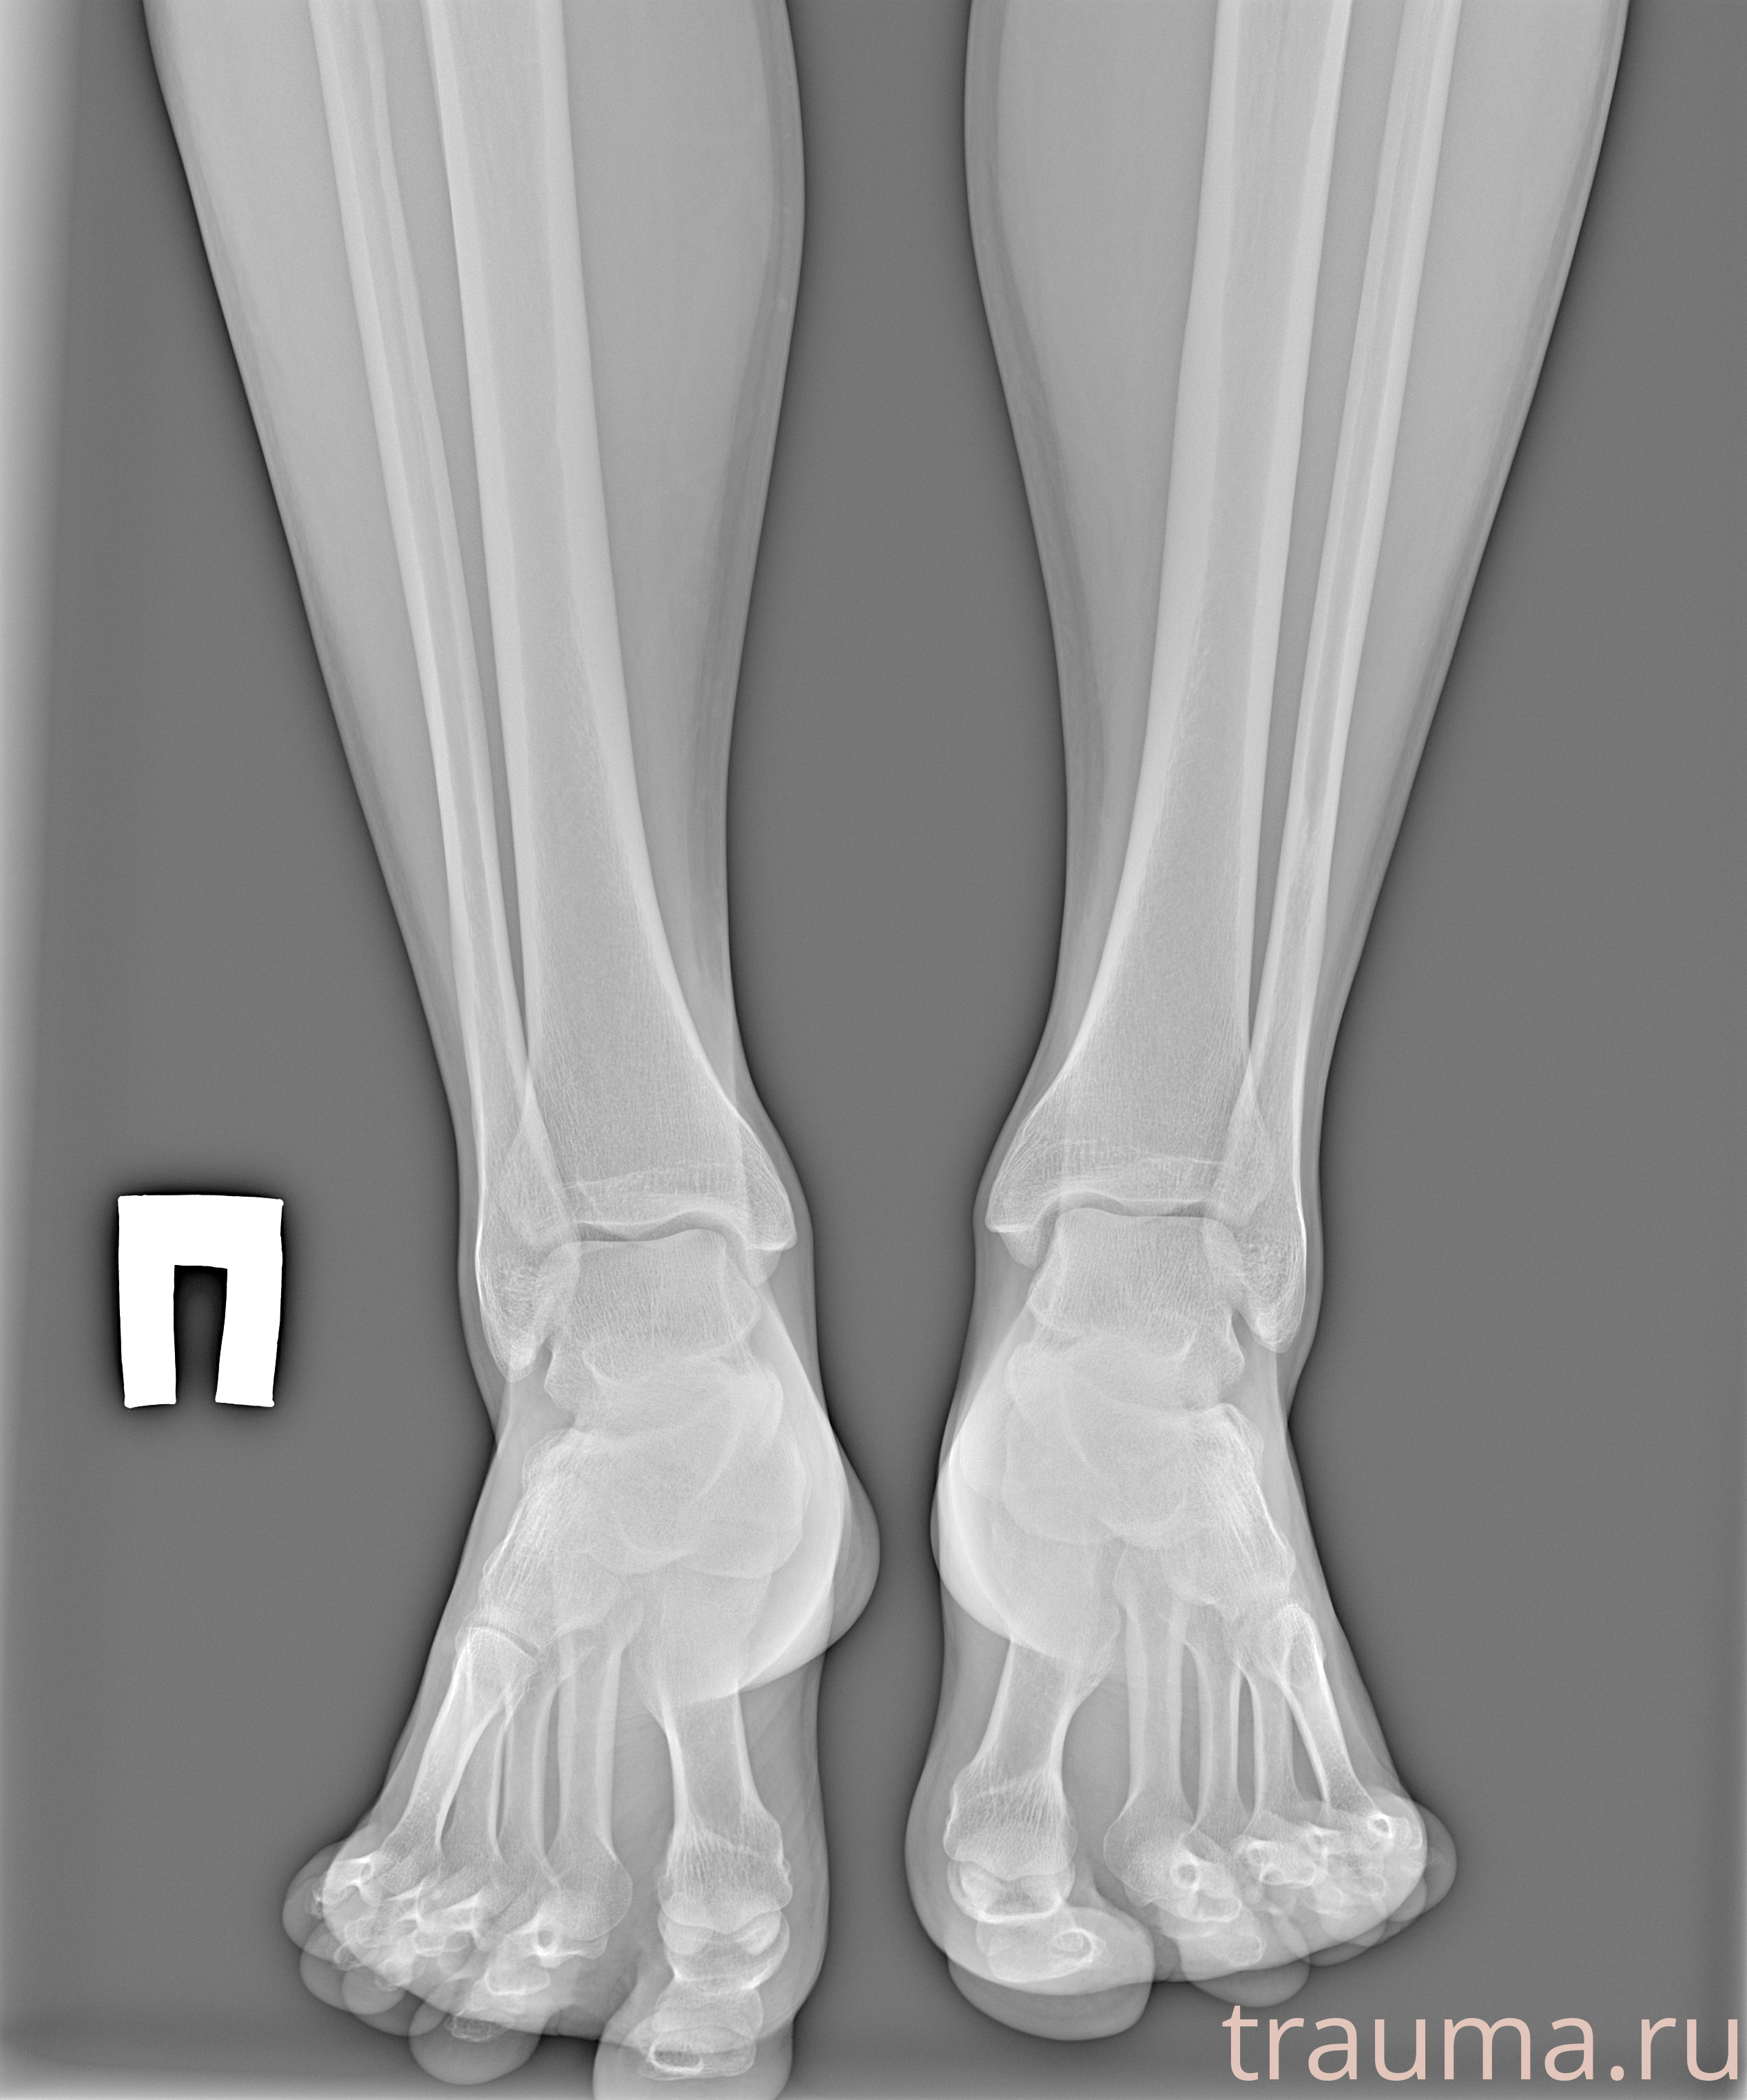

Рентгенограммы

Рентген на дому: по вашему адресу приезжает врач-рентгенолог, травматолог-ортопед с мобильным рентгеновским аппаратом, проводит диагностику травмы или заболевания, делает необходимые рентгенограммы, дает рекомендации по дальнейшему лечению. Получить качественные снимки в домашних условиях возможно благодаря уникальной методике, разработанной МосРентген Центром для института  Склифосовского